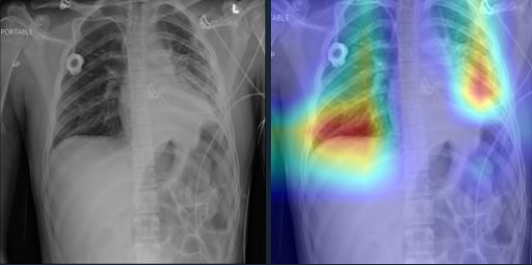

In Figure 3c the proposed model diagnoses the sample as a positive case for lung mass by detecting the right area. A lung mass is defined as an abnormal spot or area in the lungs larger than 3 centimeters (cm), about 1.5 inches, in size. Spots smaller than 3 cm in diameter are considered lung nodules. Finally, in Figure 3d, we have provided a positive case of Cardiomegaly, which is also known as an enlarged heart. In this case, the Grad-CAM mapping of our model shows that it was able to detect this condition by determining where the heart is located and especially, some edge parts of the heart.

Refer to caption

(d) Cardiomegaly

Figure 3: Grad-CAM of our model for positive samples containing Consolidation, Atelectasis, Mass, or Cardiomegaly. For each sample, the original image is shown on the left and the Grad-CAM of the 3-layer headed SwinCheX is shown on the right.